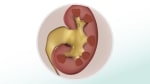

A kidney stone begins as a tiny piece of crystal in the kidney. When the urine leaves the kidney, it may carry the crystal out, or the crystal may stay in the kidney. If the crystal stays in the kidney, over time more small crystals join it and form a larger kidney stone.

Most stones leave the kidney and travel through the urinary tract when they are still small enough to pass easily out of the body. No treatment is needed for these stones.

Larger stones may become stuck in the ureters, which are the tubes that carry urine from the kidney to the bladder. This can cause pain and possibly block the urine from flowing. The pain can become severe. But it often goes away when the stone passes into the bladder. Medical treatment may be needed for larger stones.